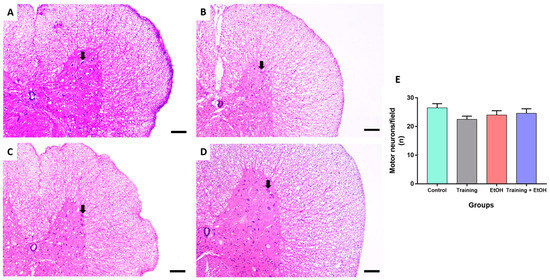

3.3. Regular Physical Training Did Not Prevent MN Density Reduction in the Cervical Segment Induced by Repeated Binge-like EtOH Intake

Binge-like EtOH intake significantly reduced the MN density in the cervical segment only when compared to the control group (‘control group’: 28 ± 1.134; ‘EtOH group’: 21.11 ± 1.419; p = 0.011; η2 = 0.188) (Figure 4). The MN density in the thoracic segment was not significantly different among groups (p > 0.05) (Figure 5). In the lumbar segment, the MN density of the ‘training group’ was significantly different in comparison to ‘EtOH group’ (‘training group’ 31 ± 2.236; ‘EtOH group’ 24.22 ± 0.702; p = 0.061; η2= 0.576); however, this difference was not significant when training was associated with binge-like EtOH intake (‘training + EtOH group’) (Figure 6).

Figure 4. Representative HE-stained photomicrographs of the cervical segment of the spinal cord of rats (100μm scale bar). (A) control group; (B) training group; (C) EtOH group, and (D) training + EtOH group. (E) Graph of MN density in each group (n = 9) expressed as mean ± standard error of the mean of the number of cells counted per field. Black arrows indicate motor neurons. Asterisk (*) indicates a significant difference (One-way ANOVA and Tukey post hoc test, p < 0.05).

This study determined the MN density in the ventral horn of the spinal cord, which is directly related to motor activity [54]. The binge-like EtOH intake protocol reduced the MN density in the cervical segment when compared to the control group, albeit no remarkable differences were observed in the thoracic and lumbar segments. Nevertheless, physical training did not provide significant protection to spinal cord cells against EtOH exposure. It may be explained by the need for longer survival times to provide neuroprotection for the MN after oxidative stress reduction, which is an acute pathological event observed in several acute and chronic neural disorders. Moreover, several populations of short- and long-range projection interneurons are also found in the spinal cord and are likely to differently respond to EtOH intoxication. Physical training may also provide neuroprotection to other cell populations rather than MN. For instance, propriospinal interneurons play a key role to synchronize motor activity and ambulation of the spinal cord [77,78] and may distinctly respond to both EtOH-induced detrimental effects and physical training-induced neuroprotective effects investigated in this study. Therefore, these hypotheses are encouraged to be addressed in further studies.